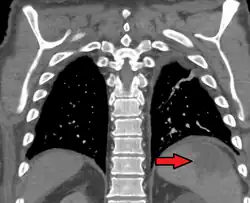

Splenic infarction is a condition in which blood flow supply to the spleen is compromised,[1] leading to partial or complete infarction (tissue death due to oxygen shortage) in the organ.[2] Splenic infarction occurs when the splenic artery or one of its branches are occluded, for example by a blood clot.[3]

An abdominal CT scan is the most commonly used modality to confirm the diagnosis,[3] although abdominal ultrasound can also contribute.[5][6][7]